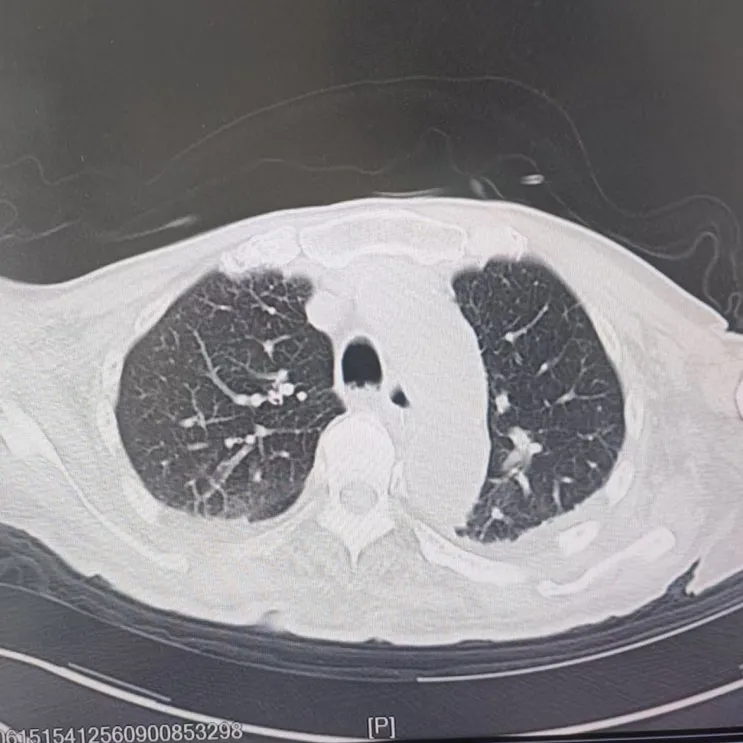

引言 / / Introduction 年近8旬的陳阿姨(化名)因腦梗長(zhǎng)期癱瘓?jiān)诖?,康?fù)期間突然高燒不退,體溫升至39℃,在抗感染過(guò)程中,她并發(fā)高滲性脫水,病情急劇惡化,被緊急送入ICU。此時(shí),她已氣管切開(kāi),依靠呼吸機(jī)維持呼吸,并伴有低蛋白血癥、低鉀高鈉血癥及房顫等多種危重情況,命懸一線! PART. 01 多重泛耐藥菌疊加大量基礎(chǔ)病 治療陷入“死胡同” 呼吸與危重癥醫(yī)學(xué)科及ICU通力協(xié)作,穩(wěn)住患者生命體征。治療過(guò)程中,進(jìn)一步的病原學(xué)檢查結(jié)果令人心驚:陳阿姨的肺部遭遇多種“超級(jí)細(xì)菌”混合侵襲,包括銅綠假單胞菌、鮑曼不動(dòng)桿菌、嗜麥芽窄食單胞菌、金黃色葡萄球菌、木糖氧化無(wú)色桿菌、粘質(zhì)沙雷菌等高度耐藥菌,堪稱(chēng)耐藥菌“大本營(yíng)”。這些細(xì)菌對(duì)常用抗生素幾乎全部耐藥,治療難度高,死亡率高。 治療前患者肺部影像 PART. 02 多學(xué)科強(qiáng)強(qiáng)聯(lián)手 量身定制攻堅(jiān)方案 面對(duì)無(wú)藥可用的困境,呼吸科沒(méi)有放棄!宋剛主任帶領(lǐng)團(tuán)隊(duì)聯(lián)合藥學(xué)部、檢驗(yàn)科、重癥醫(yī)學(xué)科成立多學(xué)科治療組,根據(jù)患者身體情況實(shí)時(shí)調(diào)整用藥,逐一攻破耐藥菌。這場(chǎng)與“超級(jí)細(xì)菌”的拉鋸戰(zhàn)持續(xù)了30多個(gè)日夜。 在醫(yī)護(hù)日夜堅(jiān)守和家屬全力配合下,陳阿姨的感染終于被遏制:高燒退了,肺部陰影消散了!就在即將宣告勝利時(shí),又發(fā)現(xiàn)她存在泌尿感染問(wèn)題,隨即轉(zhuǎn)入泌尿外科協(xié)同治療。當(dāng)宋主任回訪時(shí),看到陳阿姨精神煥發(fā)、體溫平穩(wěn),所有參與救治的人都感慨萬(wàn)分!這場(chǎng)救治,正是呼吸與危重癥醫(yī)學(xué)科攻堅(jiān)耐藥菌硬實(shí)力的生動(dòng)體現(xiàn)! 治療后患者肺部影像 從“無(wú)藥可用”到“絕處逢生”,此次成功救治,集中體現(xiàn)了呼吸與危重癥醫(yī)學(xué)科以耐藥菌精準(zhǔn)診治為核心的學(xué)科特色與技術(shù)優(yōu)勢(shì)。面對(duì)一次次的嚴(yán)峻挑戰(zhàn),科室始終秉持“生命至上、知難而進(jìn)”的信念,以多學(xué)科協(xié)作為平臺(tái),憑借個(gè)體化精準(zhǔn)用藥策略,為患者尋找生機(jī),為更多陷入困境的患者和家庭帶去了實(shí)實(shí)在在的希望。 PART. 03 人民醫(yī)院 人民名醫(yī) 宋剛 主任醫(yī)師 ·葫蘆島市第二人民醫(yī)院呼吸與危重癥醫(yī)學(xué)科主任 ·遼寧省生命科學(xué)學(xué)會(huì)東北呼吸與危重癥醫(yī)學(xué)(PCCM)分會(huì)遼寧省基層委員會(huì)副主任委員 ·遼寧省細(xì)胞生物學(xué)學(xué)會(huì)放射粒子治療專(zhuān)業(yè)委員會(huì)理事 ·遼寧省抗擊新冠肺炎疫情先進(jìn)個(gè)人 ·葫蘆島市勞動(dòng)鑒定委員會(huì)專(zhuān)家?guī)斐蓡T ·葫蘆島市醫(yī)學(xué)會(huì)呼吸內(nèi)科學(xué)分會(huì)第三屆委員會(huì)副主任委員 專(zhuān)業(yè)特色:擅長(zhǎng)呼吸系統(tǒng)疑難及急危重患者的救治,如急慢性支氣管炎、支氣管哮喘、慢性阻塞性肺疾病、肺炎、肺栓塞、肺癌、間質(zhì)性肺疾病、睡眠呼吸暫停綜合征等,尤其擅長(zhǎng)有創(chuàng)無(wú)創(chuàng)機(jī)械通氣、支氣管鏡下相關(guān)檢查及治療(TBNA、氣道支架置入術(shù)、球囊擴(kuò)張等)、全肺灌洗術(shù)等領(lǐng)先技術(shù),發(fā)表國(guó)家級(jí)期刊多篇。